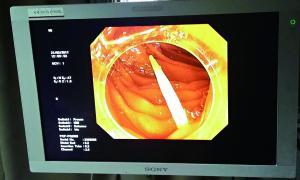

卡在腸道中的牙簽的影像檢查圖。

據(jù)中山一院胃腸外科譚進(jìn)富副主任醫(yī)師介紹,胃鏡檢查發(fā)現(xiàn),這根牙簽一路下滑,滯留在小腸,一端刺破腸道,鉆出去的部分占了三分之二長(zhǎng),引發(fā)了嚴(yán)重感染。